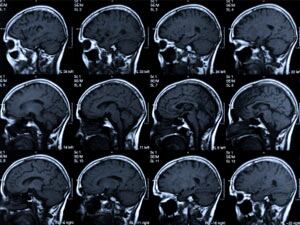

Un especialista atendrà per videoconferència els casos d'ictus que es produeixin arreu de Catalunya(Generalitat de Catalunya)

L'especialista donarà instruccions a través de videoconferència als hospitals comarcals i provincials, que d'aquesta manera tindran el suport dels especialistes de la Vall d'Hebron, Bellvitge i Can Ruti. Cada 45 minuts, a Catalunya, una persona pateix un ictus isquèmic.

Les quatre hores i mitja immediatament posteriors al moment de patir un ictus isquèmic són crítics per aconseguir recuperar el funcionament del cervell que ha patit una falta de reg sanguini per l'oclusió d'una artèria.

És per això que reduir el temps del diagnòstic per començar el tractament és clau. Amb aquesta premissa, el departament de Salut ja va posar en marxa el 2006 el Codi Ictus, un pla d'actuació que s'aprofita de les noves tecnologies per interconnectar els hospitals comarcals amb els de referència per tenir assistència d'especialistes a través de videoconferència.

Ara, el Codi Ictus fa un pas més, i 24 centres de salut no només estaran en comunicació entre ells sinó que, sobretot, disposaran d'un especialista dels hospitals Can Ruti, Bellvitge i Vall d'Hebron, que estarà permanentment de guàrdia les 24 hores del dia i els 7 dies de la setmana.

Actualment, el 12,5% dels ictus que es produeixen a Catalunya poden ser atesos amb tractaments trombolítics. La xifra s'ha triplicat en els últims 4 anys i s'equipara amb la d'Holanda, la més alta d'Europa.